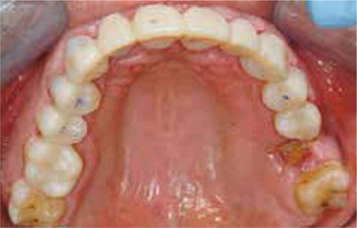

Afb. 3

Occlusaal aanzicht van de bovenkaak.

Afbeelding vergroten

Bij het extraoraal onderzoek zie ik een lichte hypertrofie van de m. masseter. Intraoraal tref ik een ernstig versleten dentitie aan waarbij de slijtage niet passend bij de leeftijd kan worden genoemd (afbeelding 2-7 en tabel 1) .